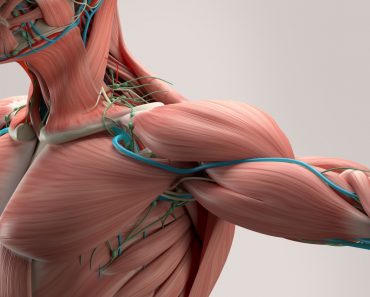

The skeleton is what supports and anchors the soft tissue of our body, such as muscles and skin. It gives mobility and a definite shape, as well as protecting us from environmental stressors. For example, the skull protects the brain, while the ribs protect the lungs and the heart.

It should be obvious that the skeleton is one of the most important parts of our body. The skeleton is made up of bones – tissue composed of structural proteins, such as collagen and minerals, primarily calcium, as well as various bone cells and blood vessels.

The appendicular skeleton is formed of all the bones other than the axial bones, such as the bones that form the arms and legs. The word “appendicular” means “limbs”.